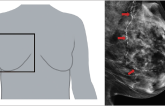

AI-Measured Breast Artery Calcification Tied to CV Outcomes in Women